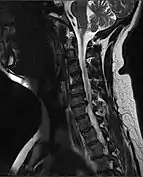

| MRI of fractured and dislocated neck vertebra that is compressing the spinal cord | |

A radiographic evaluation using an X-ray, CT scan, or MRI can determine if there is damage to the spinal column and where it is located.[9] X-rays are commonly available[85] and can detect instability or misalignment of the spinal column, but do not give very detailed images and can miss injuries to the spinal cord or displacement of ligaments or disks that do not have accompanying spinal column damage.[9] Thus when X-ray findings are normal but SCI is still suspected due to pain or SCI symptoms, CT or MRI scans are used.[85] CT gives greater detail than X-rays, but exposes the patient to more radiation,[87] and it still does not give images of the spinal cord or ligaments; MRI shows body structures in the greatest detail.[9] Thus it is the standard for anyone who has neurological deficits found in SCI or is thought to have an unstable spinal column injury.[88]